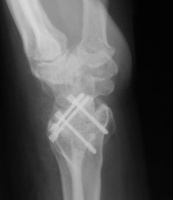

Three months postop :

Image Image Image